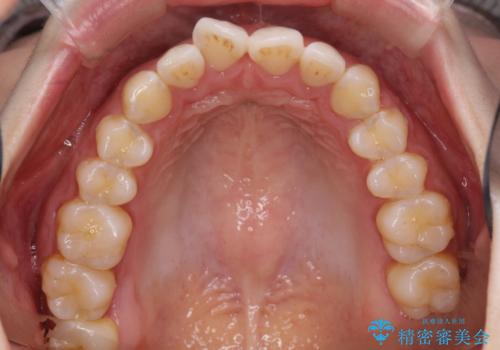

初診時の歯並びの状態としては、上下にガタガタがある状態であり、特に上の前歯(左上1番)の捻じれを最も気にしていらっしゃいました。

前歯の捻じれを改善するためにスペースを作る必要があり、前歯の歯の間を削って簡単に直す方法もありますが、奥歯のズレが認められたため、大臼歯後方のスペースを利用し、根本的な原因からしっかりと治療を行いました。